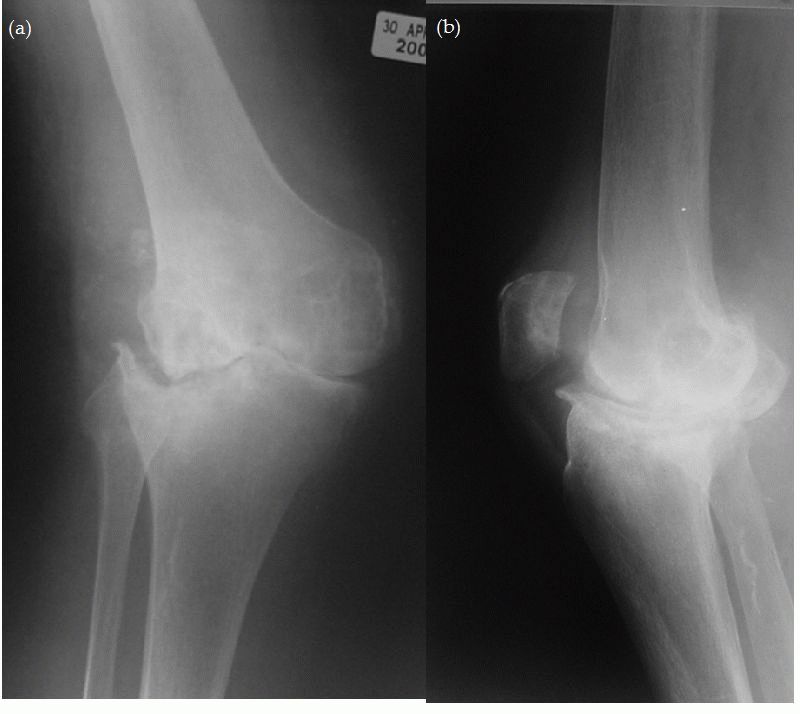

Медицинские состояния: Септический артрит коленного сустава